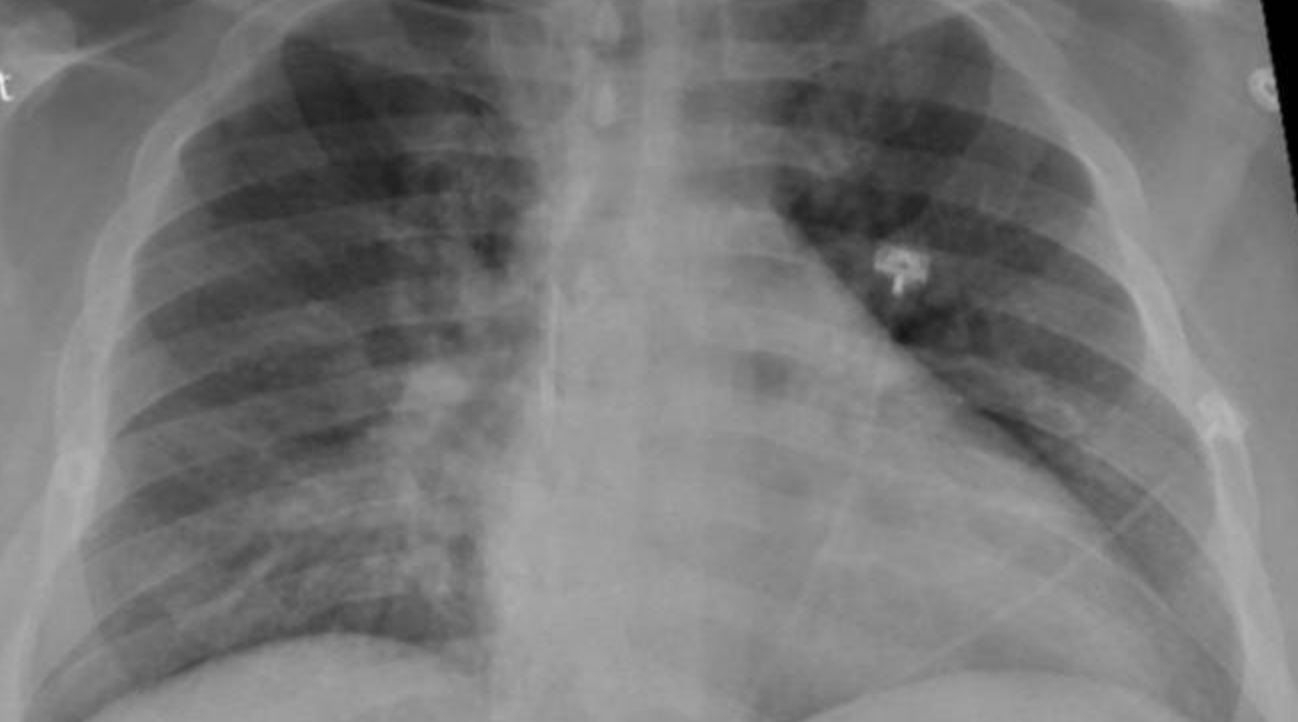

Así, estos investigadores proponen una herramienta de diagnóstico adicional para Covid-19 que proviene de las imágenes de los pulmones. Para el diagnóstico de las enfermedades pulmonares, las radiografías de tórax o las tomografías computarizadas son los principales recursos, y pueden utilizarse para distinguir la Covid-19 de otros tipos de lesiones pulmonares, así como para evaluar la gravedad de la afectación pulmonar en la Covid-19. Estos tipos de imágenes pueden mejorar la capacidad de diagnóstico de los pacientes con Covid-19, especialmente si se combinan con modelos de inteligencia artificial.

Para ello, los investigadores empezaron por utilizar un modelo para recoger automáticamente datos de imágenes de los lóbulos pulmonares. A continuación, se analizaron estos datos para obtener características como posibles biomarcadores de diagnóstico de Covid-19. Estos biomarcadores de diagnóstico mediante el modelo de inteligencia artificial se utilizaron posteriormente para diferenciar a los pacientes con Covid-19 de los pacientes con neumonía y de los sanos.

El modelo completo se desarrolló con una cohorte de 704 radiografías de tórax y, a continuación, se validó de forma independiente con 1.597 casos procedentes de múltiples fuentes compuestas por pacientes sanos, con neumonía y con Covid-19. Los resultados mostraron un excelente rendimiento del modelo a la hora de clasificar los diagnósticos de los distintos pacientes.